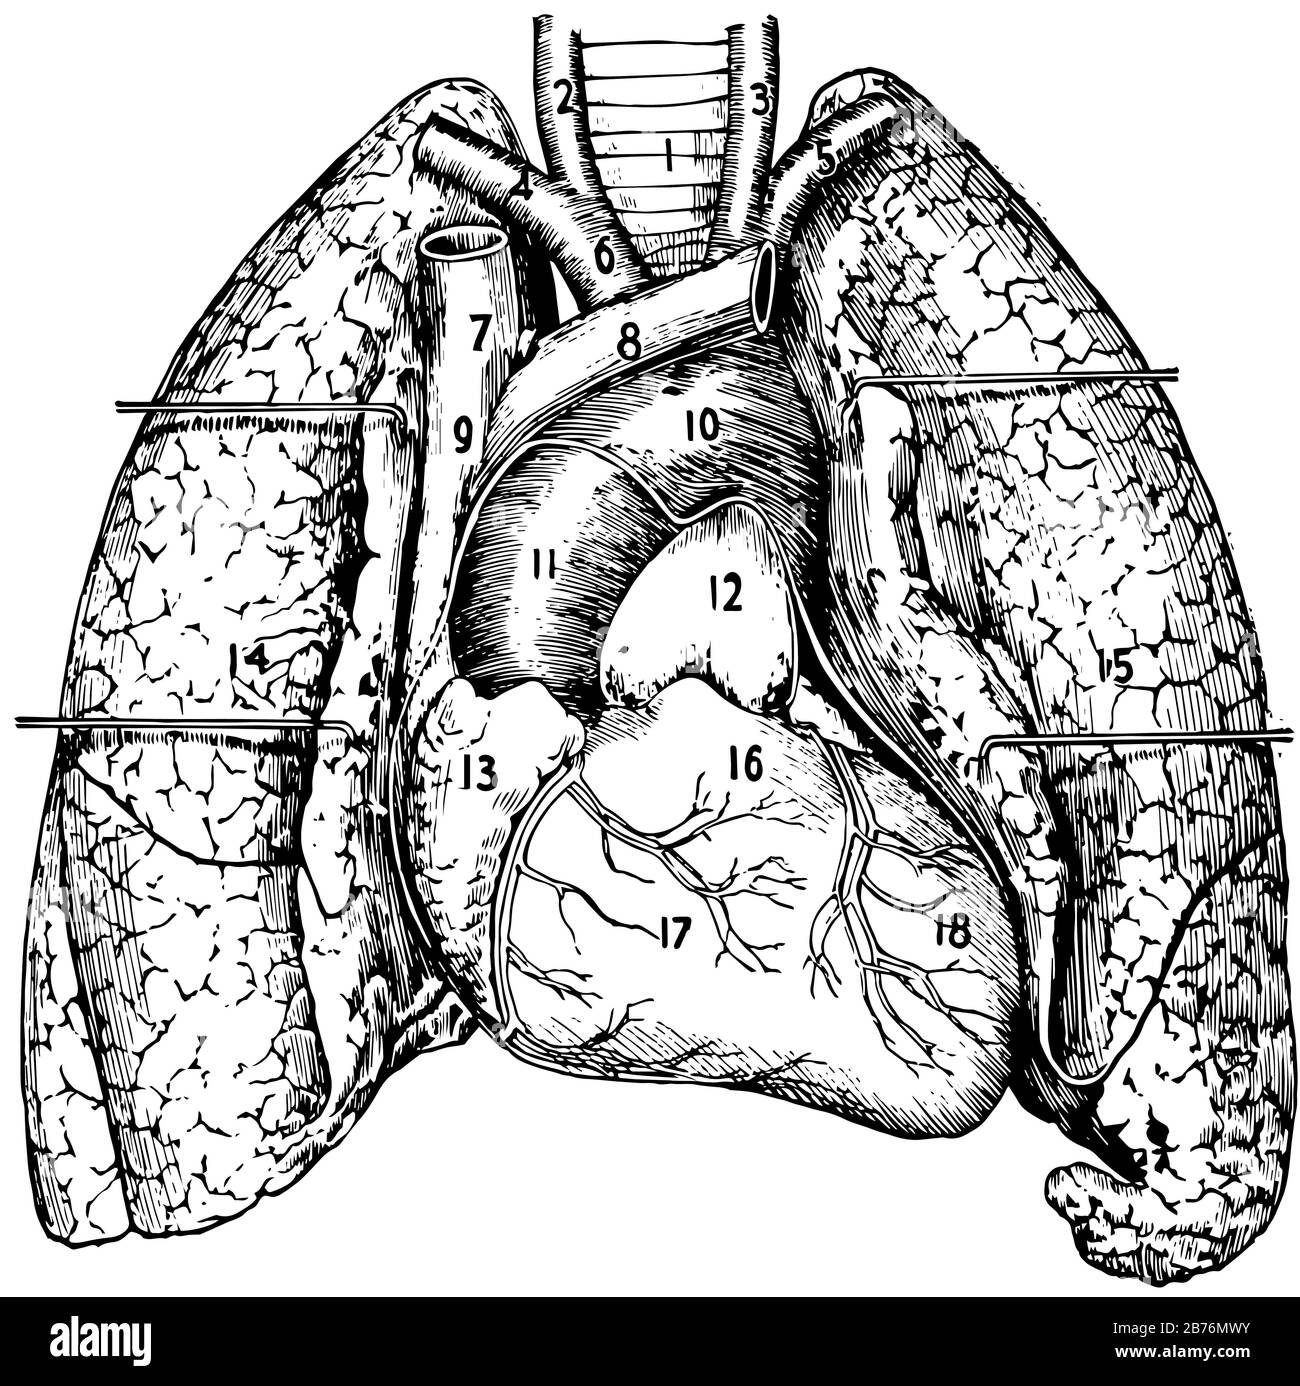

This diagram represents various parts of Heart and Lungs, vintage line drawing or engraving illustration. Stock Vectorhttps://www.alamy.com/image-license-details/?v=1https://www.alamy.com/this-diagram-represents-various-parts-of-heart-and-lungs-vintage-line-drawing-or-engraving-illustration-image348658071.html

This diagram represents various parts of Heart and Lungs, vintage line drawing or engraving illustration. Stock Vectorhttps://www.alamy.com/image-license-details/?v=1https://www.alamy.com/this-diagram-represents-various-parts-of-heart-and-lungs-vintage-line-drawing-or-engraving-illustration-image348658071.htmlRF2B76MWY–This diagram represents various parts of Heart and Lungs, vintage line drawing or engraving illustration.